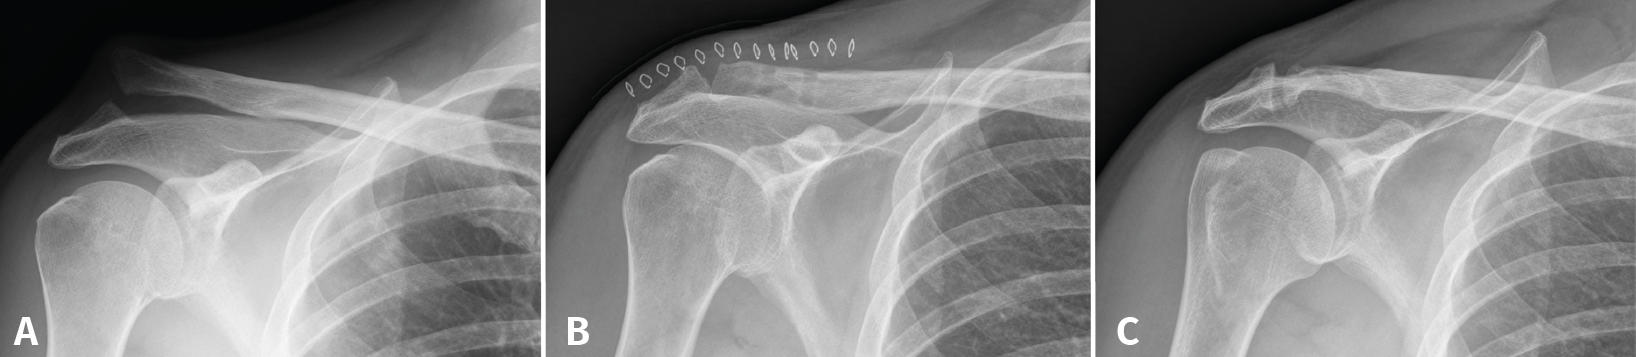

Figure 2. An 18-year-old male presenting type V acromioclavicular dislocation initially subjected to conservative management. One year after the injury he presented persistent symptoms and absolute limitation for sports activities (A). Surgery was performed with good reduction of the deformity (B), and four years after the operation the functional outcome was excellent (C), with minimum degenerative changes in the acromioclavicular joint and some widening of the clavicular tunnels.